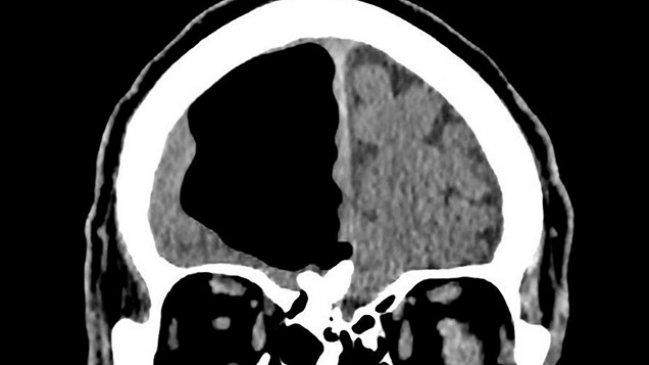

Un hombre de 84 años sorprendió a un grupo de médicos que hallaron un gran hueco de aire en el lugar donde debería ir su cerebro.

Según informó Washington Post, el espacio anormal medía cerca de nueve centímetros y es algo común en pacientes que han tenido cirugía cerebral, aunque en tamaños mucho menores. El fenómeno también podría producirse por infecciones nasales o por golpes faciales.

No fue hasta que le realizaron tomografías cuando notaron el hueco de aire en el lóbulo frontal derecho de su cabeza: una parte de su cerebro estaba desaparecida.